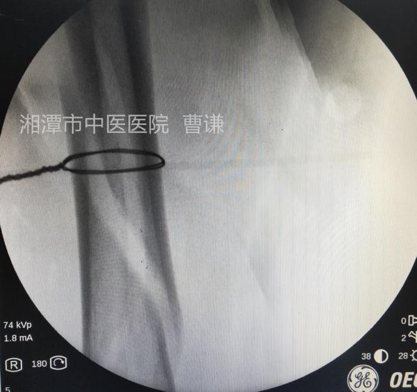

在远折端依前法再置入一根钢丝进行捆扎复位,因担心过度拧紧导致钢丝断裂,没有强求骨折解剖复位。

追求完美者可以将钢丝再拧紧一些,复位将更漂亮。

扩髓后沿导针置入髓内钉,注意尾端不要突出髁间窝,髓内钉尖端应置于小转子水平。

安装瞄准器后分别置入远端锁钉及近端锁钉,透视锁定良好。

透视侧位骨折对位对线良好,锁钉位置良好。